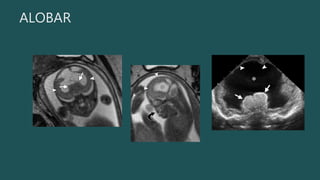

ALOBAR

US:

• UN VENTRÍCULO

PRIMITIVO

SOLITARIO Y EL

TÁLAMO

FUSIONADO

 SIGNO “ SERPIENTE DEBAJO DEL

CRÁNEO”.

• #16 Alobar HPE. (a) Axial oblique US image obtained at 18 weeks shows fused thalami (arrowheads) and a monoventricle (*). (b) Axial oblique US scan obtained at a higher level shows the cuplike morphology of the noncleaved hemispheres (arrows) “cupping” the monoventricle (*). middle and anterior cerebral arteries may be absent, replaced by a network of vessels arising from the internal carotid and basilar vessels

• #17 Figure 12. Alobar HPE. (a) Coronal fetal MR image shows a monoventricle (*), fused thalami (arrows), and minimal overlying brain tissue (arrowheads). (b) Sagittal T2- weighted half-Fourier RARE MR image shows a flattened midface (arrow) and the “ball” configuration of the remaining cortex (arrowheads) surrounding the monoventricle (*). (c) Coronal US image in the neonate confirms the single monoventricle (*), fused thalami (arrows), and minimal overlying brain tissue (arrowheads).